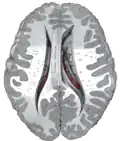

This is a transverse view of the caudate nucleus from a structural MR image.

Transverse view of the caudate nucleus from a structural MR image